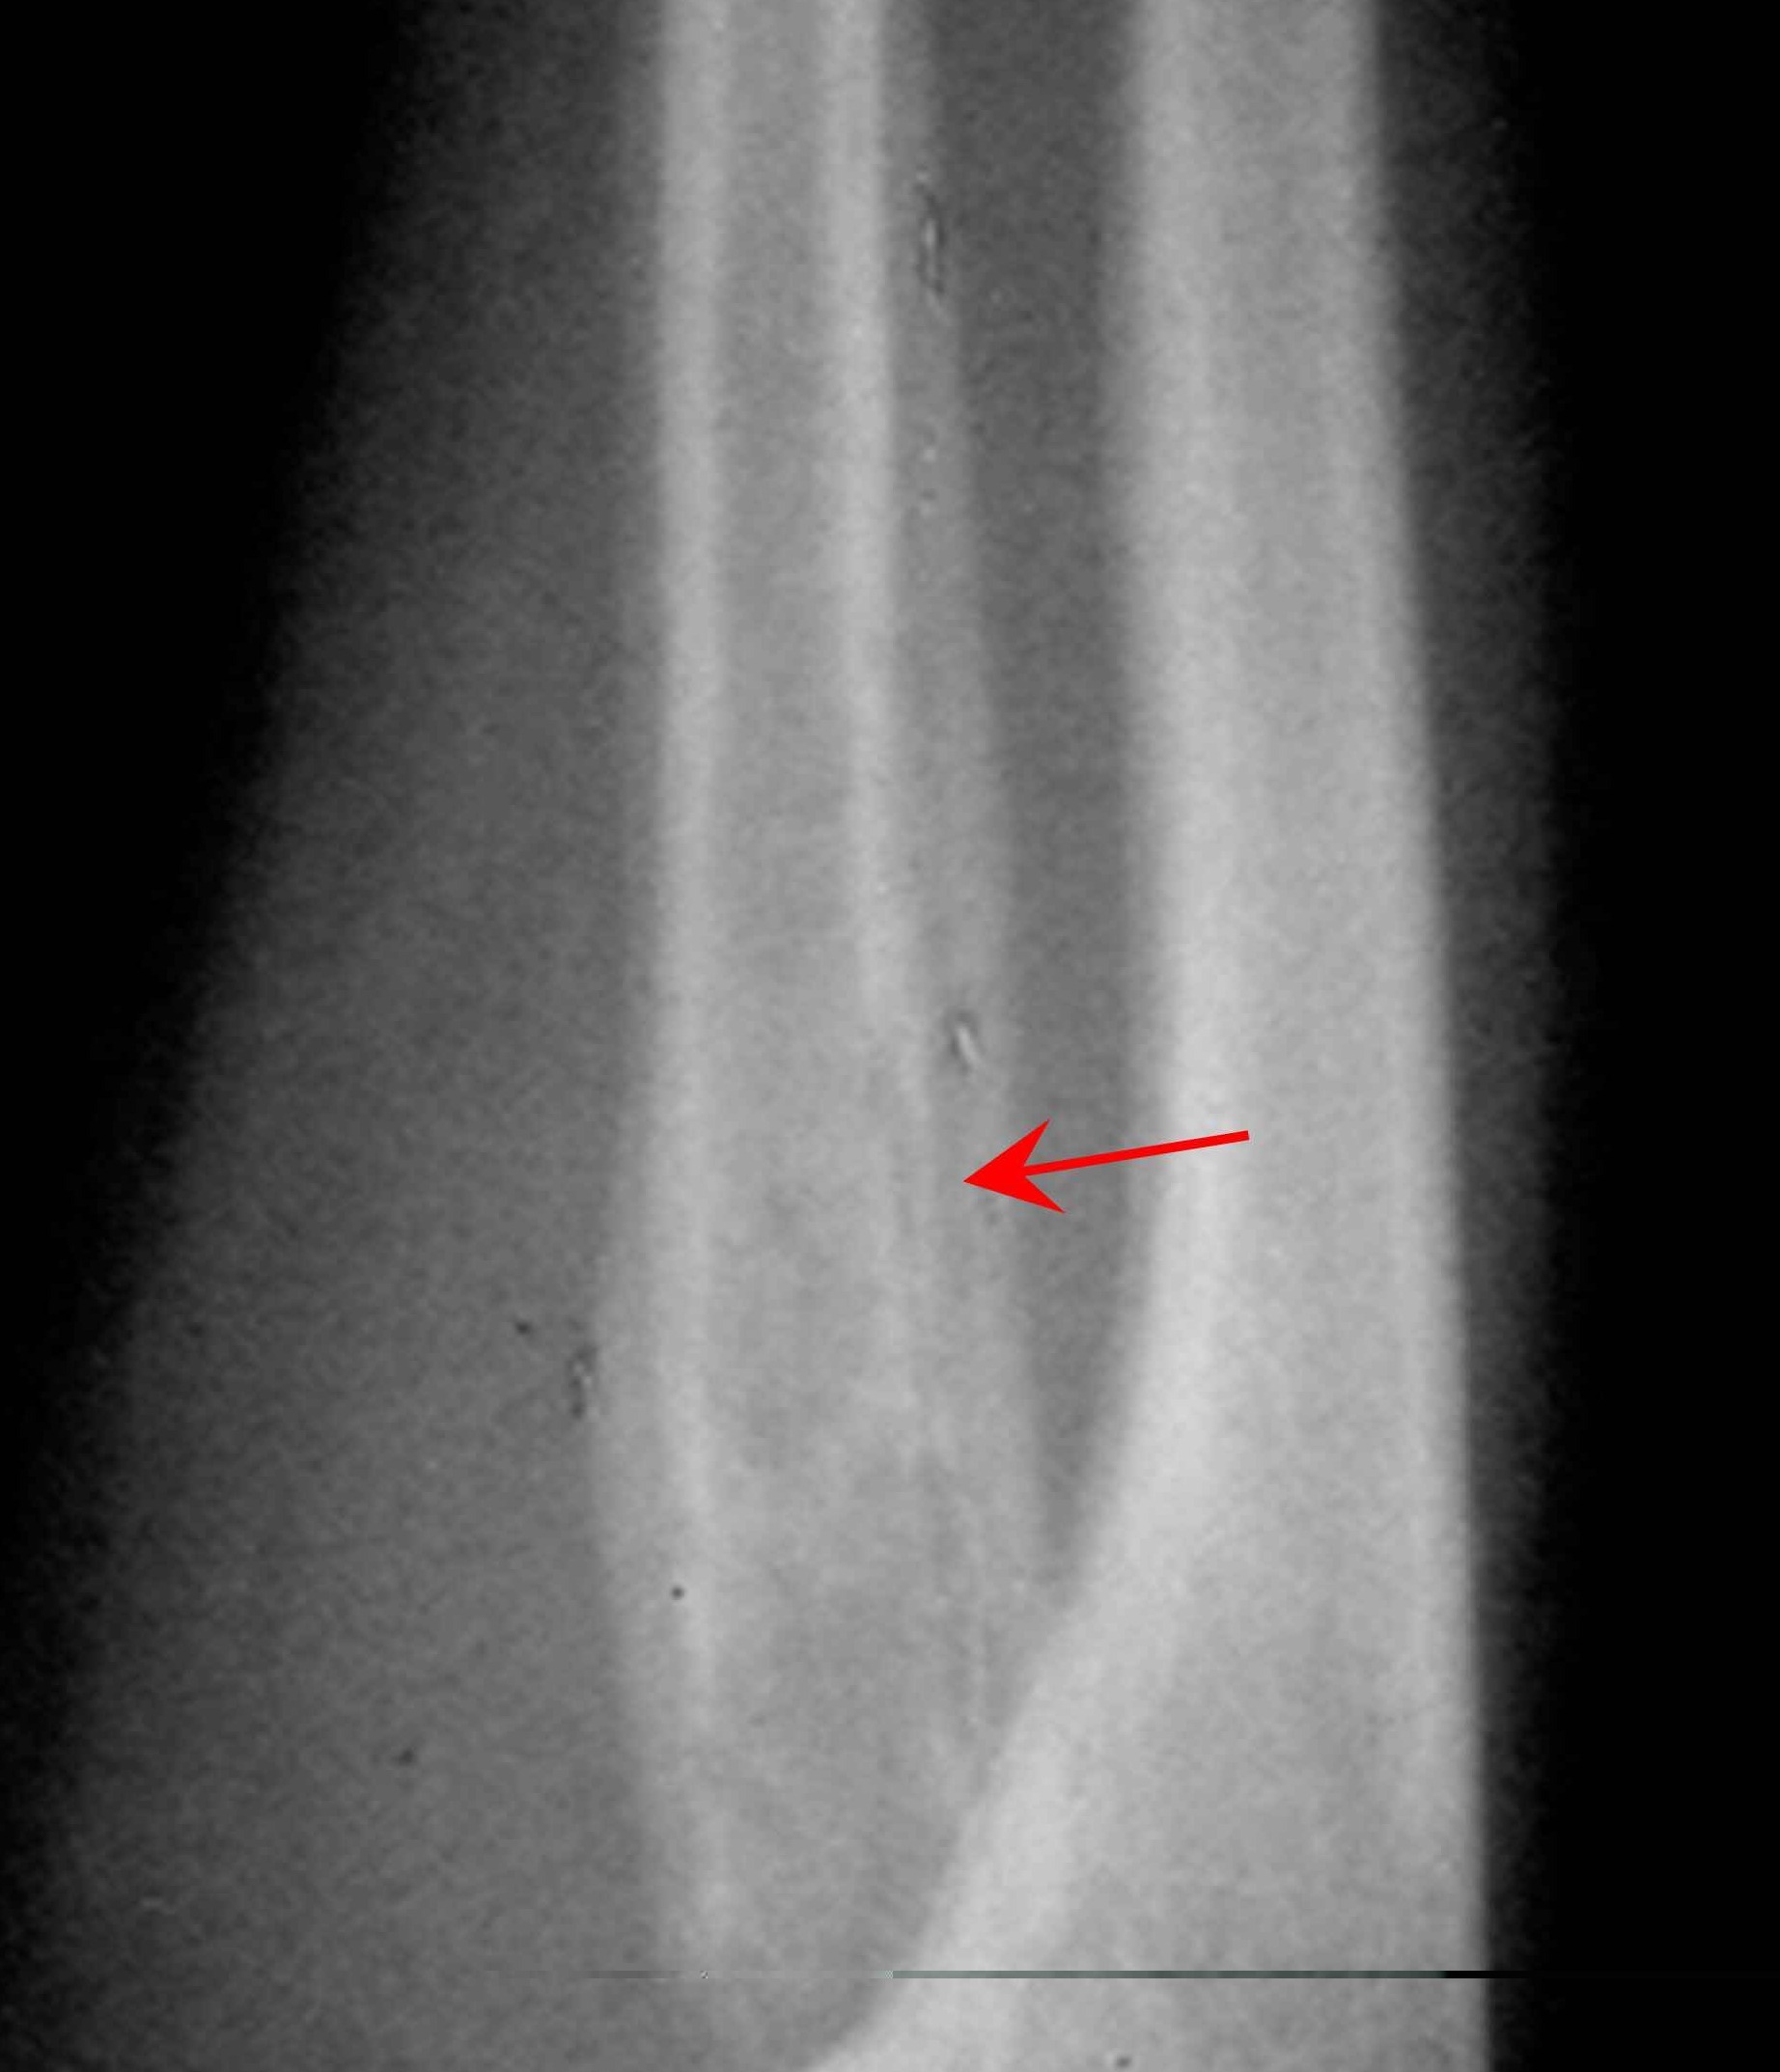

在临床表现上,骨髓炎又分为急性骨髓炎和慢性骨髓炎。急性骨髓炎主要以破坏坏死为主,慢性骨髓炎主要以炎性增生为主,不管是哪一种骨髓炎,都是要非常谨慎的去治疗的,如果没有在初期得到很好的治疗,导致伤病恶化,就会使后期的治疗过程变得艰难,因为骨髓炎形成的窦道是很恐怖的,开始时可能只有一个小小的窦道,这时候没有得到有效的治疗,就会恶化扩大,致使患处大面积的溃破。